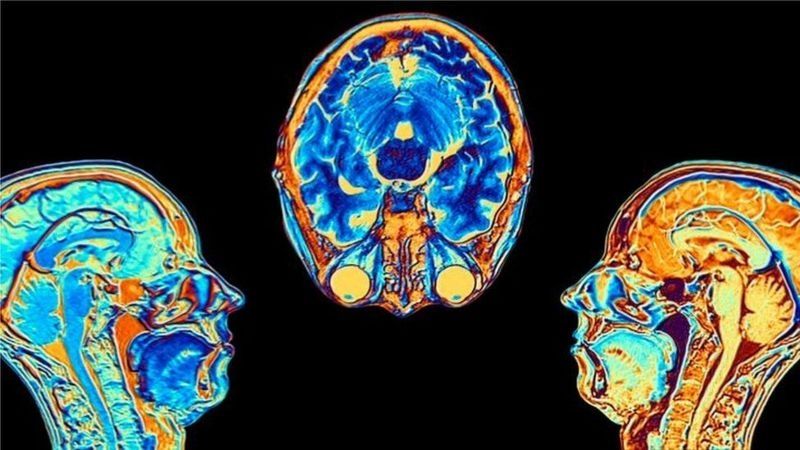

Contagiarse de covid-19 puede provocar cambios en el cerebro, según indicó un estudio publicado en la revista Nature.